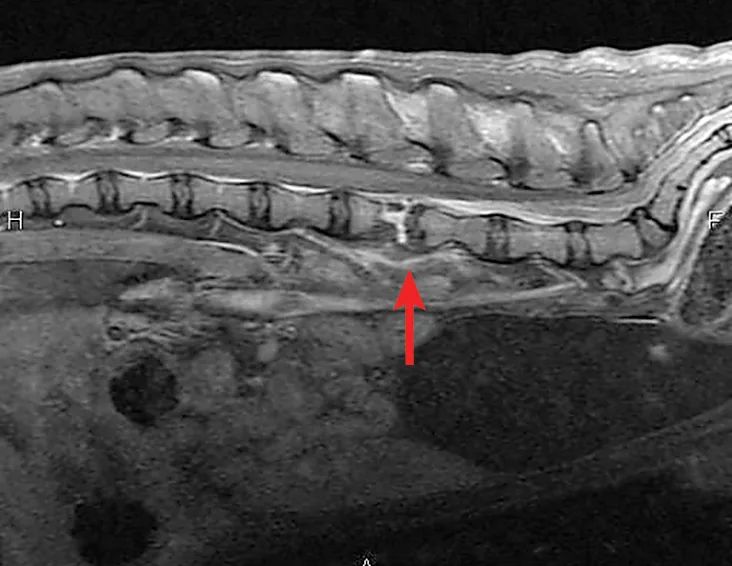

Lateral radiograph of the patient’s vertebral column. Narrowing of the L4-L5 space, reduction of the L4-L5 foramen, and an irregular lucent cleft at the level of the caudal endplate of L4 can be seen (arrow).

A lateral radiograph of Jax's vertebral column revealed narrowing of the L4-L5 intervertebral disk space, reduction of the L4-L5 intervertebral foramen, and an irregular lucent cleft at the level of the caudal endplate of L4 (Figure 1). These findings were most consistent with physitis (see Discussion) and an associated end plate fracture.